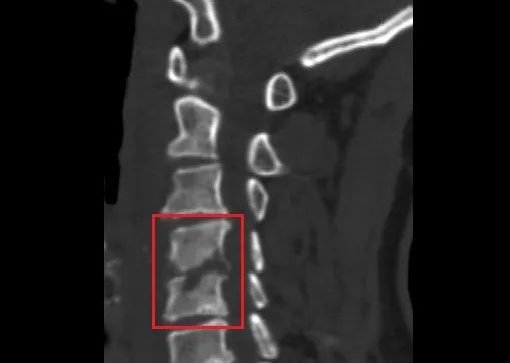

福建长乐漳港的王女士颈肩部反复疼痛,近日去医院就诊,CT检查把所有人吓了一跳。她得的是“颈椎结核”,而且C4、C5两节颈椎已经被“吃掉”近一半,有瘫痪的风险。

在医院疼痛科,王女士做了影像检查,医生发现她的颈椎周围形有大量脓肿,C4、C5椎体的骨质已经被吞噬得“面目全非”,出现了几处明显的缺口。

如图,红圈部分↓↓↓

文章插图